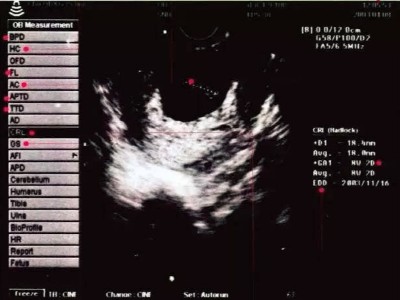

妈妈们在怀孕期间一般情况下需要做4-5次的彩超检查,每一次的检查对于妈妈们来说都尤为重要,那么,当妈妈们拿到B超纸时,看到上面的一些专业词,B超纸该如何看呢?下面,小编就为大家来介绍一下。

B超报告单中,孕妈咪经常看到以下一些专业词,它们到底是什么意思呢?

1、CS 为胎囊只在怀孕早期看到,一般停经35天,B超就可在宫腔内看到孕囊。在怀孕1.5个月时孕囊直径约2厘米,2.5个月时约5厘米。

胎囊位置可能在子宫的宫底、前壁、后壁、上部、中部,形态圆形、椭圆形、清晰为正常。

2、CRL 为头臀距表示胎体纵轴平行测量最大的长轴,主要用于判定孕7-12周的胎龄。

3、BPD 为胎头的双顶径表示头部左右两侧之间的最宽距离,又叫头部最大横径,可以依此推定宝宝的体重和发育情况。

4、FL为胎儿股骨长 即大腿长度, 用于和BPD一起推算宝宝的体重。

5、枕额径 宝宝鼻骨到枕骨隆突的距离,也就是宝宝的头从前到后最长的距离。

6、头围环头一周的长度,用于确认宝宝的发育状态。

7、腹围即腹部周长,宝宝肚子一周的长度。

8、GP 为胎盘分级孕晚期(28孕周)开始,B超报告单上会出现胎盘分级。一般胎盘分为0,I ,II,III级,有时还有III+级。

I级标志胎盘基本成熟;

II级晚标志胎盘已经成熟;

III级晚标志胎盘已衰老,由于钙化和纤维素沉着,使胎盘输送氧气及营养物质的能力降低,胎儿随时有危险。

9、AFI 为羊水指数做B超时,以孕妇的脐部为中心,分上,下,左,右4个区域,将4个区域的羊水深度相加,就得到羊水指数,孕晚期羊水指数的正常值是8-18厘米。

10、 S/D为胎儿脐动脉收缩压与舒张压的比值,与胎儿供血相关,当胎盘功能不良或脐带异常时此比值会出现异常,在正常妊娠情况下,随孕周增加胎儿需要增加S下降,D升高,使比值下降,近足月妊娠时S/D小于3。